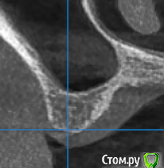

gum Опубликовано 30 ноября, 2018 Поделиться Опубликовано 30 ноября, 2018 (изменено) Здравствуйте коллеги.Подскажите как лучше сделать латеральное окно не повредив кровеносный сосуд? И лучше 1 или 2 окна сделать? Изменено 30 ноября, 2018 пользователем gum Ссылка на комментарий

kladoffka Опубликовано 30 ноября, 2018 Поделиться Опубликовано 30 ноября, 2018 Если умеете делать закрытый синус, то я бы порекомендовал его. Раза 4 пересекал сосуд - всегда успешно его забивал коллаполом. Если пойдете на осл делайте одно окно посредине. 2 Ссылка на комментарий

Борис80 Опубликовано 30 ноября, 2018 Поделиться Опубликовано 30 ноября, 2018 +1 за закрытый синус, условия более чем подходящие Ссылка на комментарий

gum Опубликовано 30 ноября, 2018 Автор Поделиться Опубликовано 30 ноября, 2018 По месту 16 - 4 мм кости, планировал имплантат на 10,0, поэтому решил ОСЛ, если закрытый, то имплантат 8,5 брать длину? Просто поднимать закрытым 7 мм еще не приходилось. Ссылка на комментарий

Борис80 Опубликовано 30 ноября, 2018 Поделиться Опубликовано 30 ноября, 2018 8,5 более, чем достаточно, можно и короче даже... но по срезам на вид побольше даже места Ссылка на комментарий

Aquarius Опубликовано 1 декабря, 2018 Поделиться Опубликовано 1 декабря, 2018 Тут закрытым надо идти и не усложнять себе жизнь Ссылка на комментарий